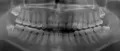

Здравствуйте,Олег! На зубе мудрости (повернут фиссурой к щеке) глубокий кариес. Болей никаких при зондировании кариозная полость твердая,не размягченная. Рентген показал кариозную полость до пульпы 0,8мм. Можно ли вылечить такой зуб?

Здравствуйте Оксана, чисто теоритически, вылечить возможно любой зуб, при наличии доступа к нему. Однако, с учетом того, что это зуб мудрости и он дистопирован (смещен) и не несет никакой функциональной нагрузки, его лечение нецелесообразно.